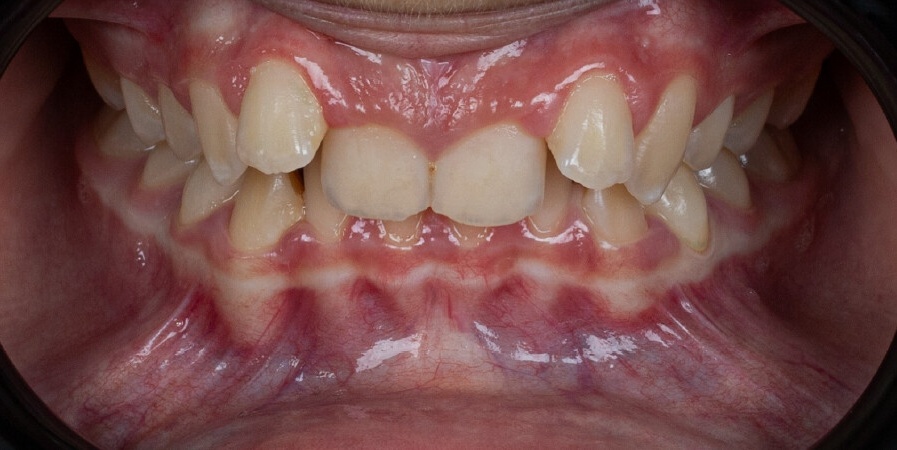

A 13-year-old patient with Class II Division 2 malocclusion and deep bite was treated using Angel Aligner A6 Mandibular Advancement. The protocol combined mandibular advancement, arch expansion, incisor intrusion, and refinement with Class II elastics, achieving functional bite correction and improved smile aesthetics in 10 months.